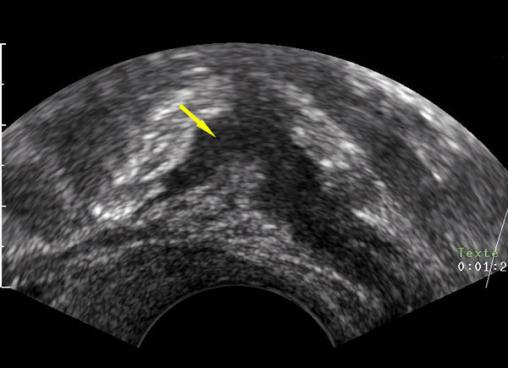

Échographie endovaginale en coupe sagittale passant en arrière du vagin montrant une masse hypoéchogène allongée remplaçant la musculeuse digestive typique d’atteinte endométriosique de la charnière recto-sigmoïde. Tiré de : Darai É, Bazot M, Ballester M. Endométriose. Rev Prat 2010;60:603-9.